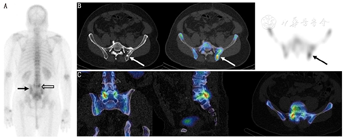

目前,越来越多的证据表明18F-FDG PET/CT在骨转移全身治疗效果监测方面具有优势(图3)。一些小型回顾性系列报道表明,SUVmax的改变可以监测骨转移的治疗反应并预测骨相关事件发生及乳腺癌骨转移疾病进展时间[42,43,44]。有2项小型前瞻性研究证实,在预测骨相关事件的发生或疾病进展时间方面,18F-FDG PET/CT优于18F-fluoride[14,45]。而18F-fluoride可能受闪烁现象的影响,无法将由闪烁现象引起的18F-fluoride摄取增加同早期疾病进展引起的摄取增加区分开来。相比之下,虽然18F-FDG显像中这种闪烁现象未得到广泛认可,但一项关于贝伐珠单克隆抗体(简称单抗)抗血管生成治疗联合化疗的肺癌患者的小型队列研究表明,该类患者的18F-FDG显像也出现了代谢闪烁现象[46]。某些患者的不同骨转移灶治疗反应可能在18F-FDG和18F-fluoride显像中存在差异,这也成为肿瘤越来越常见的现象[14]。

3.18F-fluciclovine PET/CT。作为一种氨基酸类似物,18F-fluciclovine显像会显示正常骨髓摄取。尽管如此,临床数据仍表明,其对骨转移灶的检出较骨显像更有优势(图4)[20,21]。但迄今为止,尚不清楚该显像剂在骨转移治疗反应监测中的作用。